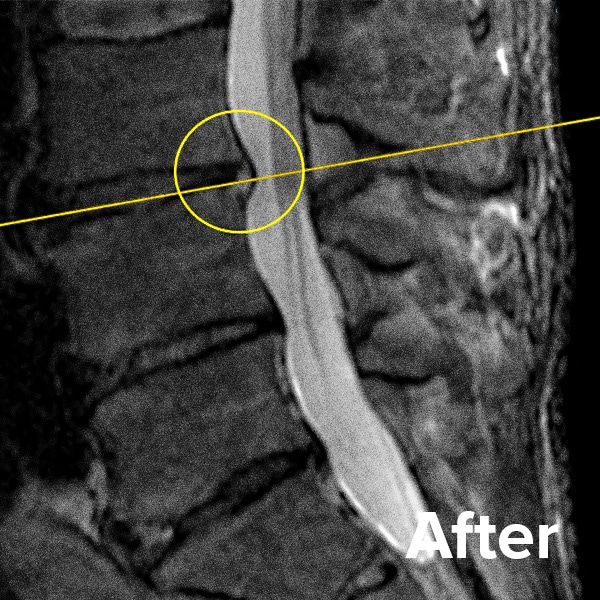

Herniated Disc MRI

Below are MRI images of the outcome of a patient who had a Regenexx PL-Disc procedure to treat a subligamentous disc herniation. After the procedure, their pain dropped quickly, and they returned to their normal activities within weeks.

Scroll the arrow to the right to see the MRI of the disc before the Regenexx PL-Disc procedure — the white/lighter area indicates damage. Scroll to the left to see the MRI of the disc after. The images are two years apart from the original treatment date.

Herniated disc before and after MRI images 1